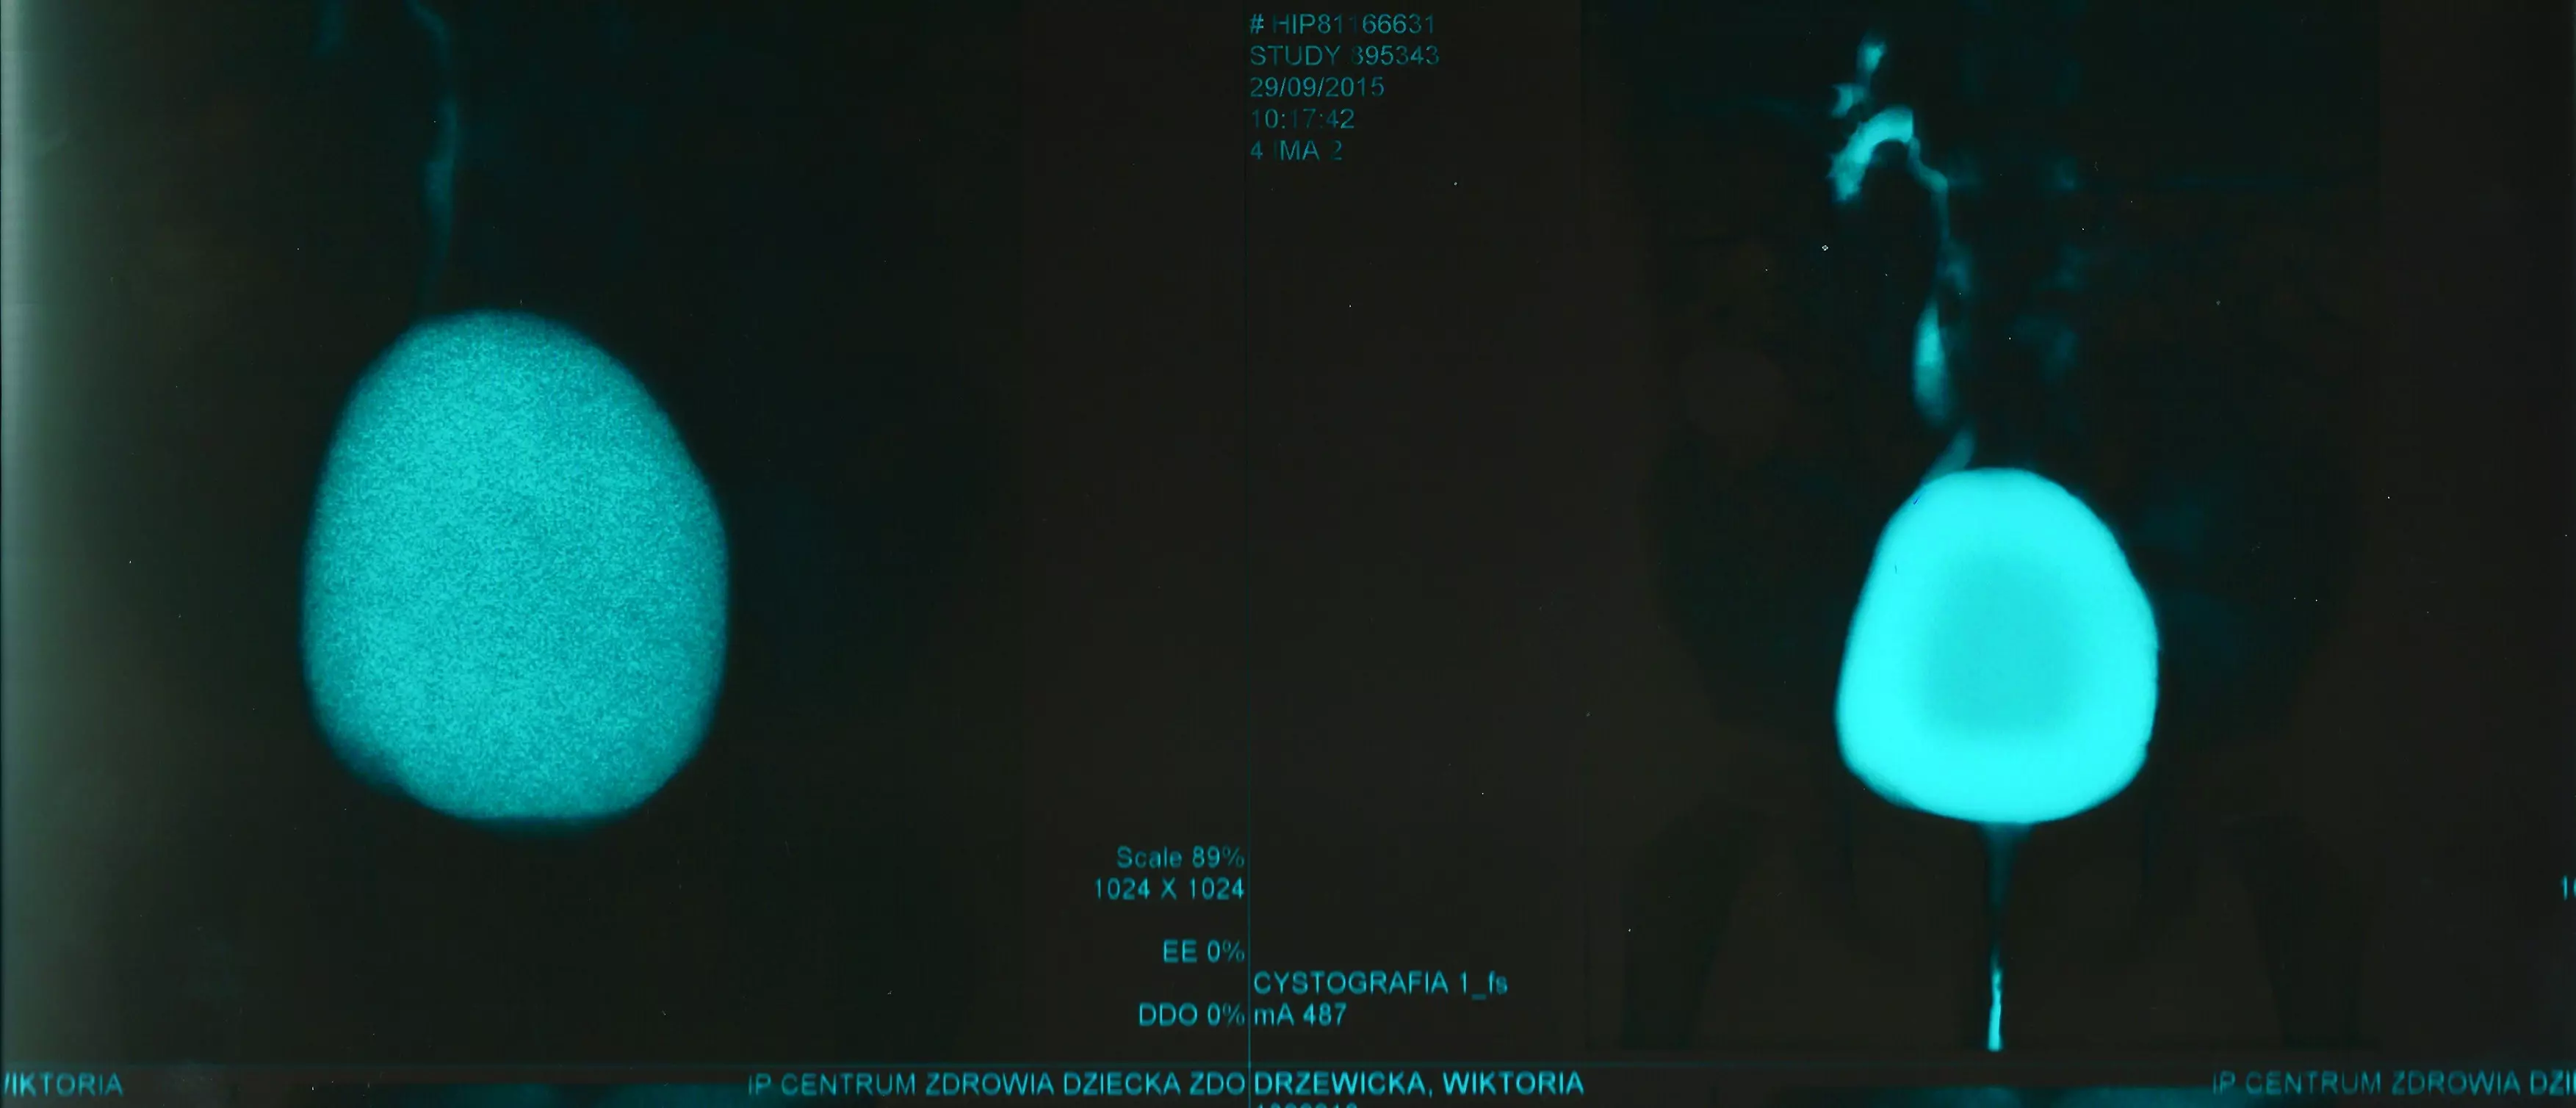

Czternastomiesięczna dziewczynka, u której stwierdzano w rejonie dwukrotnie zapalenie pęcherza moczowego z towarzyszącą gorączką, pozostająca na leczeniu profilaktycznym Furaginą, została skierowana do szpitala celem pilnej diagnostyki układu moczowego. W wykonanym wcześniej w rejonie badaniu USG nie wykazano wady układu moczowego ani zastoju w drogach moczowych. Pomimo prawidłowego obrazu nerek w badaniu USG zdecydowano o wykonaniu scyntygrafii DMSA, w której stwierdzono typowe położenie nerek (ryc. 3).

Ryc. 3. Wynik badania scyntygrafii DMSA

Nerka prawa była mniejsza niż lewa, nerka lewa o nierównych zarysach dolnego bieguna i wykazywała nierównomierne rozmieszczenie znacznika w miąższu. Współczynnik względnej funkcji nerek: nerka lewa – 60%, prawa –

40%. Wnioski: „Funkcja wydzielnicza nerki lewej w normie. Zmiany pozapalne w dolnej części nerki lewej. Upośledzona czynność wydzielnicza nerki prawej. Zmiany pozapalne w nerce prawej w szczególności w górnym biegunie”. Po uzyskaniu powyższego wyniku podjęto decyzję o wykonaniu cystografii mikcyjnej. Opis badania: „do pęcherza podano 120 ml rozcieńczonego kontrastu. W czasie badania uwidoczniono obecność prawostronnego biernego i czynnego odpływu pęcherzowo-moczowodowego II stopnia. Pęcherz moczowy o nieco nierównych zarysach z szeroką szyją. Cewka moczowa prawidłowa. Mikcja swobodna. Zarzucanie kontrastu do pochwy podczas mikcji. Po mikcji bez zalegania kontrastu w pęcherzu” (ryc. 4).

Ryc. 4. Wynik badania cystografii mikcyjnej